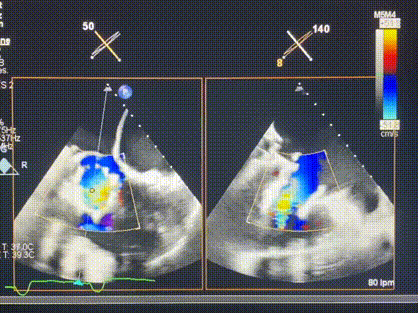

術(shù)前超聲提示重度三尖瓣反流

接受本次LuX-Valve Plus治療的是一位三尖瓣重度反流的高齡女性,患者早前曾由于二尖瓣疾病行經(jīng)導(dǎo)管二尖瓣置換術(shù),植入Tendyne瓣膜一枚,且有ICD植入史。術(shù)前CT分析結(jié)果顯示,瓣環(huán)大小為47.6mm,血管無明顯迂曲和鈣化。由于患者三尖瓣解剖結(jié)構(gòu)復(fù)雜,二尖瓣位人工瓣膜造成的超聲偽影和ICD導(dǎo)線的干擾使得歐洲沒有其他合適的商業(yè)化和臨床試驗的產(chǎn)品可以對其進行治療。經(jīng)過Rodrigo Estévez-Loureiro教授團隊的詳盡術(shù)前評估,認為LuX-Valve Plus經(jīng)導(dǎo)管三尖瓣置換系統(tǒng)可以對該患者進行有效的治療。因此,Rodrigo Estévez-Loureiro教授團隊最終決定使用這一中國創(chuàng)新器械為患者進行手術(shù)。法國波爾多里爾大學(xué)附屬醫(yī)院的Thomas Modine教授與加拿大圣保羅醫(yī)院的Anson Cheung教授全程線下指導(dǎo)本次手術(shù)。

術(shù)后超聲顯示僅殘余微量瓣周漏

LuX-Valve Plus經(jīng)血管三尖瓣置換系統(tǒng)此次“出海”圓滿完成,術(shù)后Rodrigo Estévez-Loureiro教授對LuX-Valve Plus經(jīng)血管三尖瓣置換系統(tǒng)的器械性能和治療效果大為稱贊,認為LuX-Valve Plus的手術(shù)體驗非常好。術(shù)后即刻超聲顯示三尖瓣反流幾乎完全消失,血流動力學(xué)改善顯著,患者恢復(fù)快。在面對復(fù)雜解剖結(jié)構(gòu)、超聲影像質(zhì)量不佳、有起搏導(dǎo)線干擾時,Lux-Valve Plus也體現(xiàn)了極強的適應(yīng)性。Thomas Modine教授和Anson Cheung教授也肯定了LuX-Valve Plus術(shù)中操作的便捷性,認為LuX-Valve Plus容錯率高,對術(shù)中影像的依賴較小,后期希望可以更多的應(yīng)用LuX-Valve Plus三尖瓣置換系統(tǒng)于臨床實踐,讓更多的三尖瓣重度反流患者盡早獲益,改善預(yù)后。